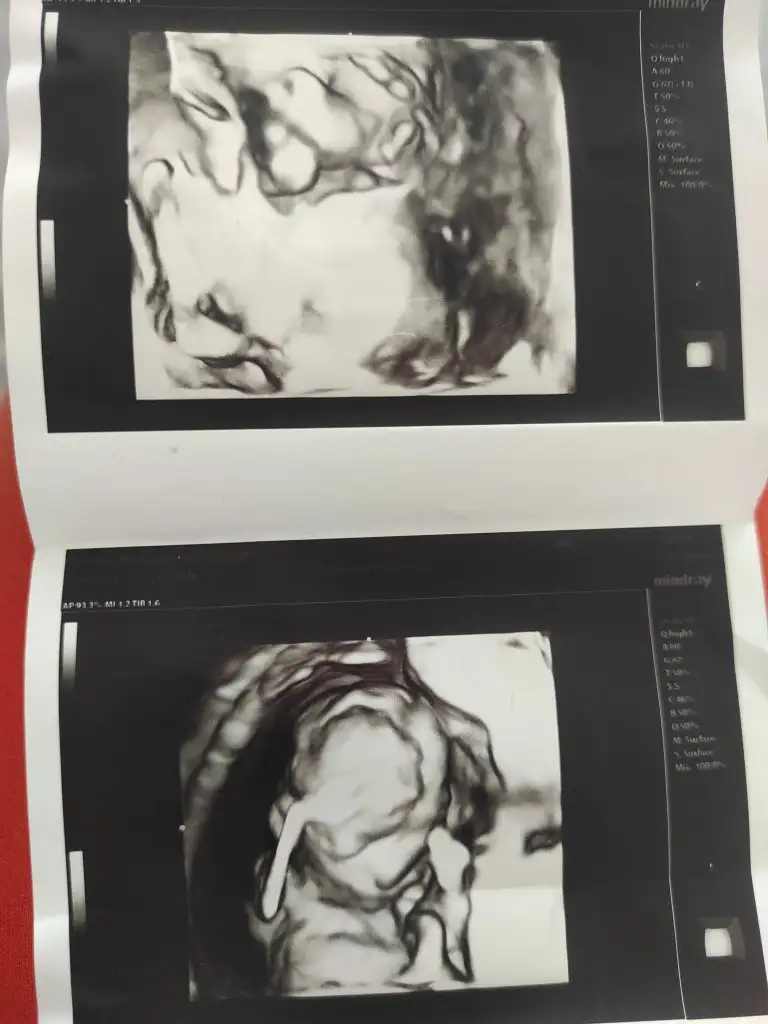

Merhaba . Nubu gozukmuyor ama kafa ve çene yapısı erkek gibi. Sağlıkla gelsin inşallahKızlar 9 yasinda bir kizim var ikinci gebeligim cinsiyet tahmini yapar misiniz görüntülerin biri 8haftalık diğeri 12 haftalık

Erkek gibi canımKızlar 9 yasinda bir kizim var ikinci gebeligim cinsiyet tahmini yapar misiniz görüntülerin biri 8haftalık diğeri 12 haftalık

Erkeğe benzettimKızlar 9 yasinda bir kizim var ikinci gebeligim cinsiyet tahmini yapar misiniz görüntülerin biri 8haftalık diğeri 12 haftalık

Kız gibi canımBınu da bakar mısn

Eki Görüntüle 3420218 15 haftalık